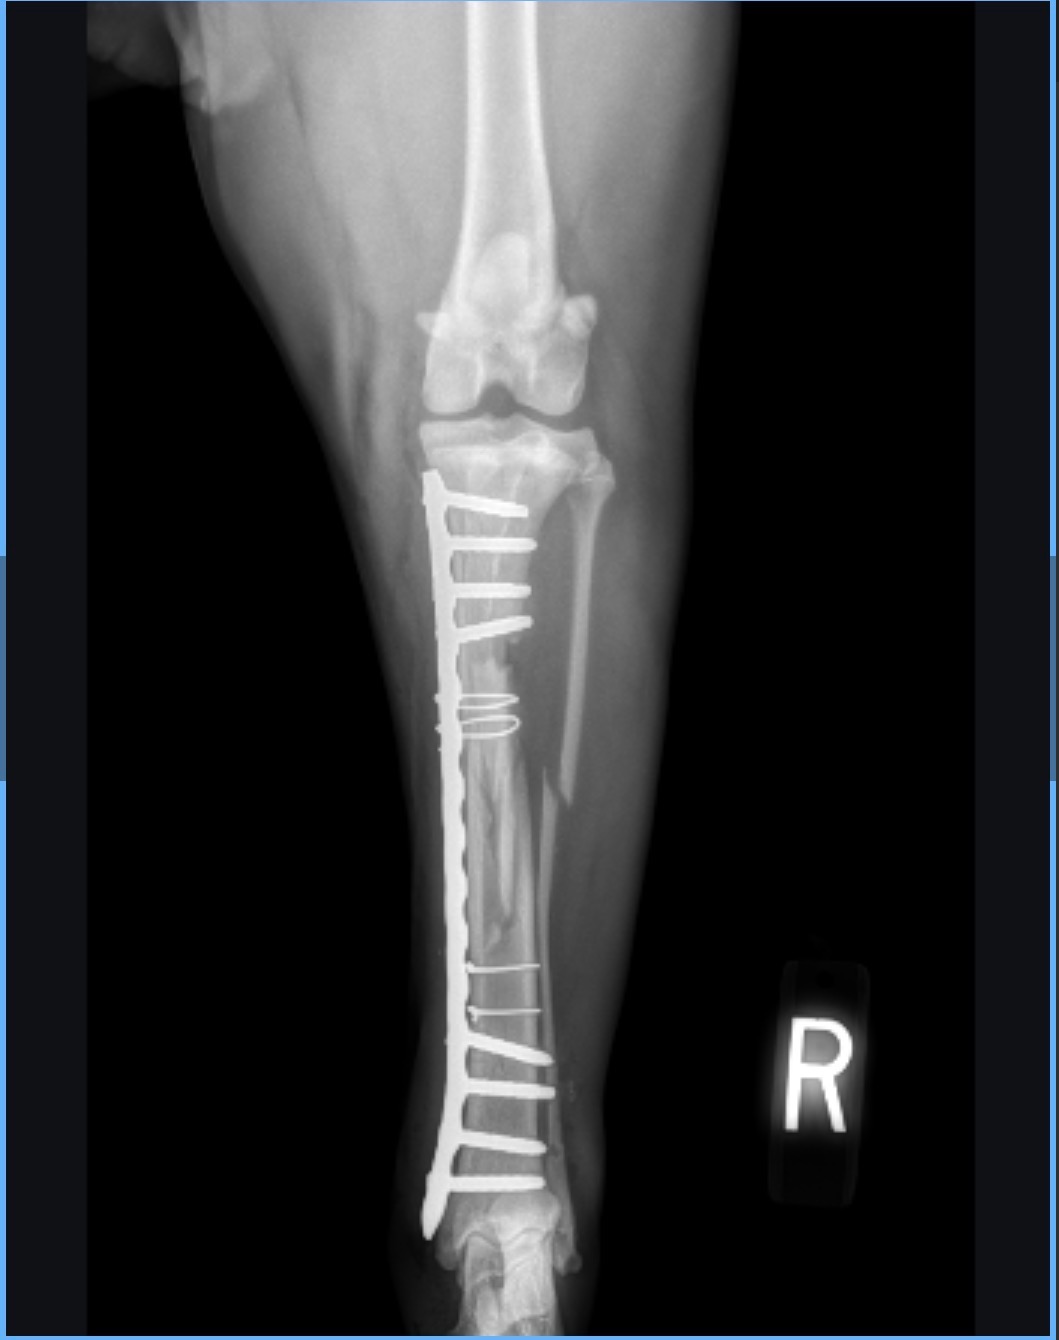

The McFarland family is raising money to support our puppy, Yuki, with her $25,000 vet bill after she broke her leg and developed a soft tissue infection. With treatment, she is improving but as the bills stack up, we are struggling to make ends meet. We are having to drive her to a veterinary hospital 96 miles from our home, as we live in a remote location and don’t have many options for care. We don’t want anyone to feel obligated to donate but any help greatly appreciated. Your support would mean Yuki can continue to go to check ups, get her medication, and return to her healthy and happy self. Supporting this GoFundMe would also mean that we are able to make ends meet during this very stressful time. Thank you for donating!